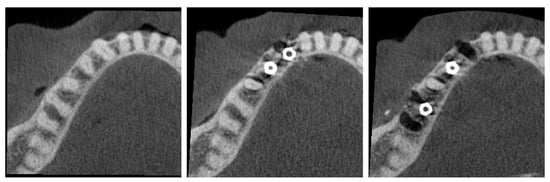

Prior to implant placement, the cadaver underwent cone beam computed tomography (CBCT) scanning (C0; Figure 1). Following tooth extraction, pilot holes were drilled using the surgical kit of the Nucleoss brand implant system, with continuous saline irrigation for cooling. In single-rooted tooth regions, drilling was directed toward the root apex, whereas in multi-rooted areas, it was aimed at the center of the inter-radicular septum. Implant osteotomies were prepared to accommodate implants with a diameter of 4.1 mm and a length of 12 mm. In accordance with the manufacturer’s guidelines, drilling was performed at 35 Ncm torque and 20 rpm. Upon completion of the final drilling, the implants (Nucleoss T6, 4.1 mm diameter/12 mm length; NucleOSS, İzmir, Turkey) were placed into the osteotomy sites without irrigation. Implant placement was conducted in accordance with two predefined configurations (Figure 1):

Figure 1. (Left) C0 configuration (no implants). (Middle) C1 configuration (adjacent implants). (Right) C2 configuration (distant implants).

• C1—Configuration where two implants are side by side, that is, there are no teeth between the implants.

• C2—Configuration with a tooth between the implants.